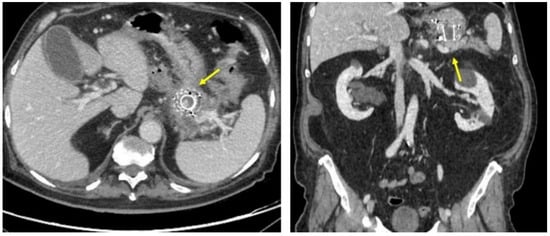

Figure 1.

Abdominal CT scan showing the presence of multiple confluent fluid collections extending from the head to the tail along the entire pancreatic profile (outlined from yellow arrow).

After four weeks, the patient was in good clinical condition, asymptomatic. An abdominal CT scan showed a reduction of the overall pseudocysts (Figure 6). The laboratory exams showed CRP, amylase, lipase, transaminases, and cholestatic exam results within the normal ranges.

Figure 6.

Abdominal CT scan showing a reduction of the overall pseudocysts (yellow arrow).